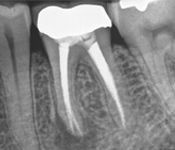

Pictured: Preoperative, Retreatment, Apicoectomy

and 5 Year Recall

Our patient required root canal retreatment. After an apicoectomy, the removal of the root tip and the infected tissue, there was complete bone healing in the 5 year recall.